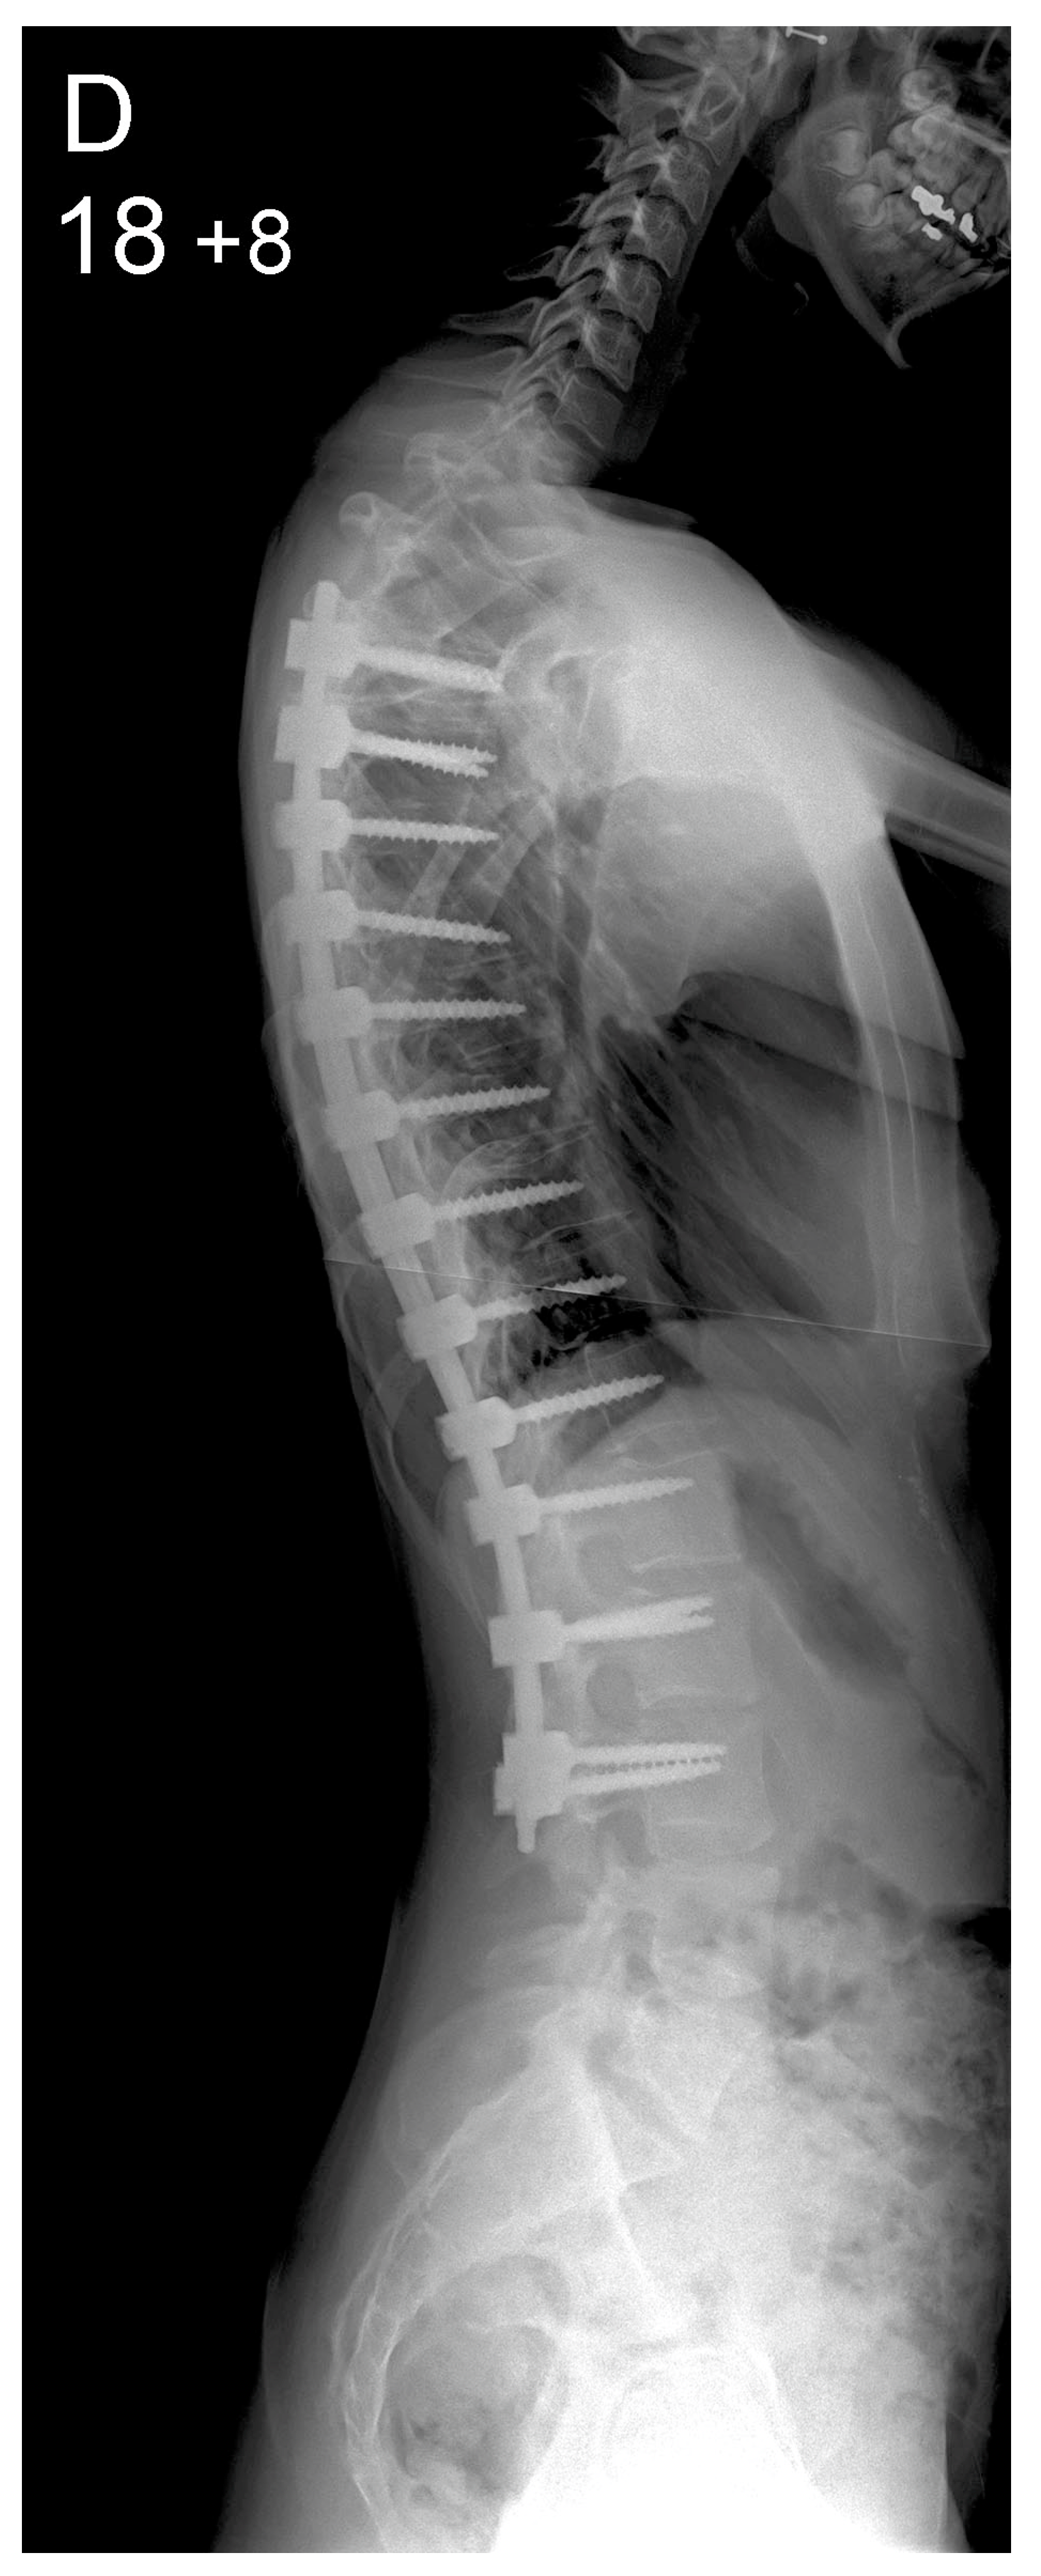

Figure 1.

Patient aged 15 years and 9 months with a right thoracic AIS producing thoracic translocation and listing of the trunk to the right, as well as thoracic flat back producing negative global sagittal balance of the spine and compensatory cervical kyphosis (A,B). The patient underwent posterior scoliosis correction using the AS technique which restored segmental and global coronal/sagittal spinal balance at latest follow-up (age 18 years and 8 months) into adult life (C,D). Clinical photographs demonstrate excellent correction of the coronal deformity and associated rib hump after scoliosis surgery (E–H).